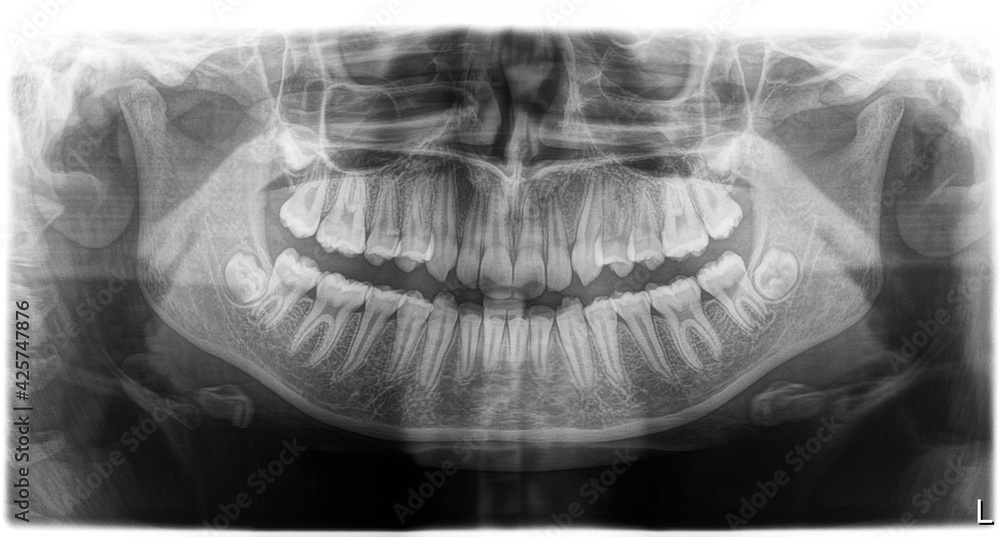

Impacted wisdom tooth. Coloured panoral Xray of the mouth of a patient with an impacted wisdom Impacted wisdom tooth In the X-ray picture photo above, the impacted wisdom teeth are clearly marked Impacted wisdom tooth causing pain? Learn symptoms, treatment options, and when removal might be the best choice for relief. Unfortunately, these molars can become impacted, meaning they don't have enough space to fully erupt through the gums in.

Source: gerryaikgf.pages.dev Impacted wisdom tooth hires stock photography and images Alamy , Impacted wisdom tooth In the X-ray picture photo above, the impacted wisdom teeth are clearly marked If you're concerned about your wisdom teeth, it's important that your dentist refers you to have an x-ray before deciding on whether or not to have them removed or treated

Source: chelsiamil.pages.dev Impacted Wisdom Tooth and Pericoronitis , The lower left eighth tooth is unerupted and impacted against the root of the 7th tooth, lying horizontally within the mandible The tooth is inverted and is associated with cystic degeneration of bone with extensive resorption necessitating considerable bone resection and facial deformity

Source: citilawtid.pages.dev Impacted Wisdom Teeth on an Xray Picture with an Inflamed Cyst Neoplasm. Removal of Wisdom , The lower right eighth tooth is partially erupted but in a reasonable position Pell & Gregory Class II impacted third molar with a radiolucent lesion extending to the neck of the condyle

Source: usaonlyqft.pages.dev Impacted Wisdom Teeth Panoramic , The lower left eighth tooth is unerupted and impacted against the root of the 7th tooth, lying horizontally within the mandible Impacted wisdom teeth can lead to oral health problems such as infection, tooth decay and gum disease